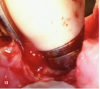

Fig 13. The VMIS technique for treating implants with bone loss incorporates disinfecting the implant surface with only a saline-soaked gauze. The use of acidic disinfecting solutions, such as hydrogen peroxide or tetracycline solutions, is avoided because they cause corrosion of the titanium oxide layer and shedding of titanium particles.

Figure 13